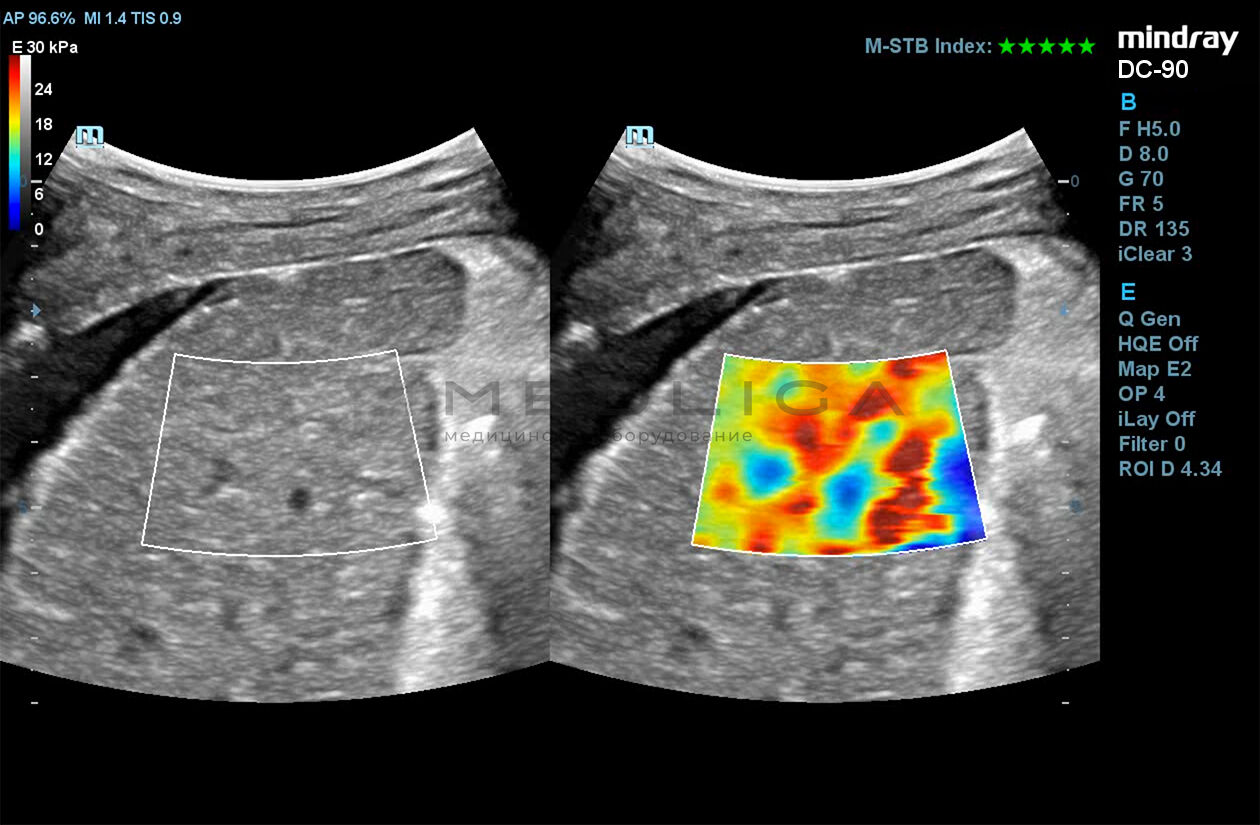

Программное обеспечение для оценки эластичности ткани методом эластографии сдвиговой волны (метод 2D-с формированием двухмерной цветовой эластограммы и количественной оценкой эластичности) на линейных и конвексных датчиках.

STE интегрирована с эксклюзивной технологией Ultra-Wide Beam Tracking от Mindray для двумерной эластографии сдвиговой волной в реальном времени. Специализированные измерительные инструменты позволяют проводить количественный анализ модуля упругости с высокой точностью.

Опция работает:

• на линейных датчиках

• на конвексных датчиках